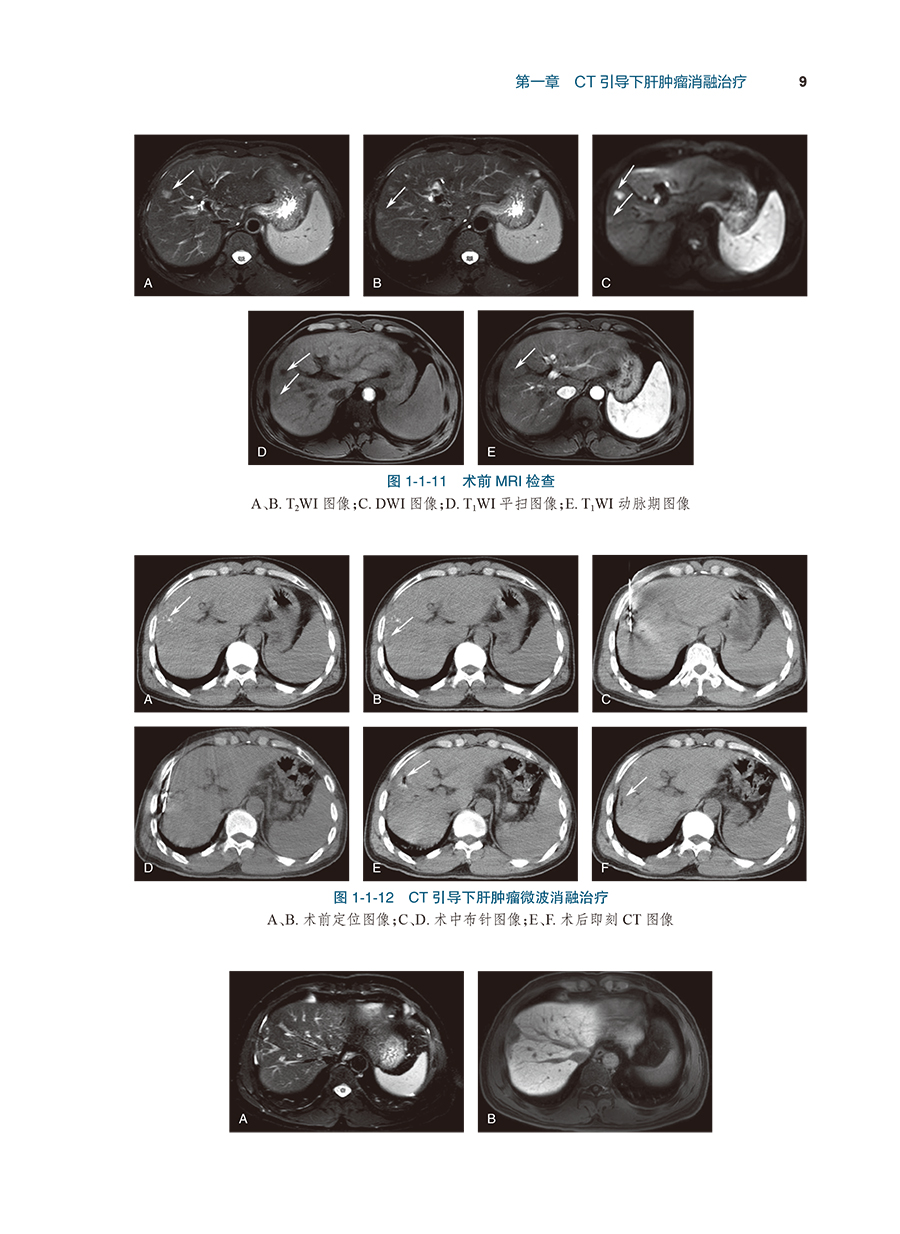

病例3肝包膜下小肝癌的微波消融治疗/8

病例4术后复发小肝癌的消融治疗/10